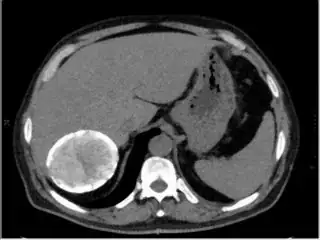

Below are some of the opened and segmented images. Of course there's more to be done in terms of

- separating out the liver region

- generalizing this to a large dataset

but hope this is at least a starting point.

You might be able to narrow down the region or interest by filtering out the darkest and the lightest regions from the segmented image. For this, use the k-means cluster centers, check for the extreme values (max and min) and remove the corresponding k values from the labeled image. Then you can look for large structures to the left of the result image. Worst case, you might get a hole on the left side when the extreme region filtering goes wrong. I've updated the code and results.